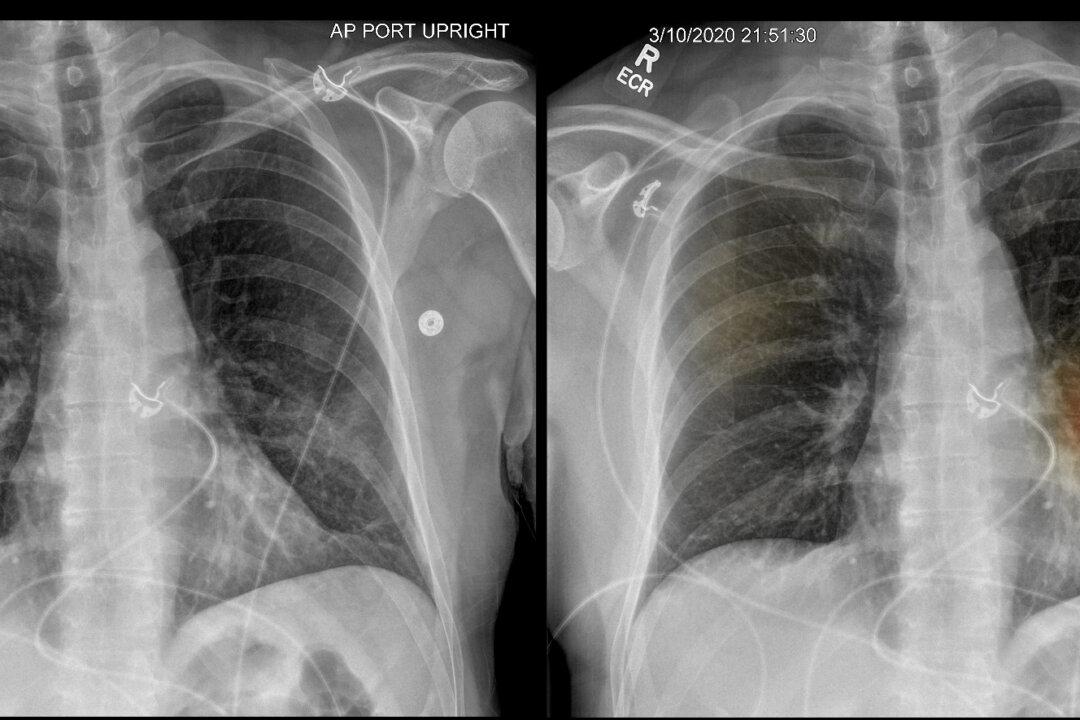

Dr. Albert Hsiao and his colleagues at the University of California–San Diego health system had been working for 18 months on an artificial intelligence program designed to help doctors identify pneumonia on a chest X-ray. When the coronavirus hit the United States, they decided to see what it could do.

The researchers quickly deployed the application, which dots X-ray images with spots of color where there may be lung damage or other signs of pneumonia. It has now been applied to more than 6,000 chest X-rays, and it’s providing some value in diagnosis, said Hsiao, the director of UCSD’s augmented imaging and artificial intelligence data analytics laboratory.